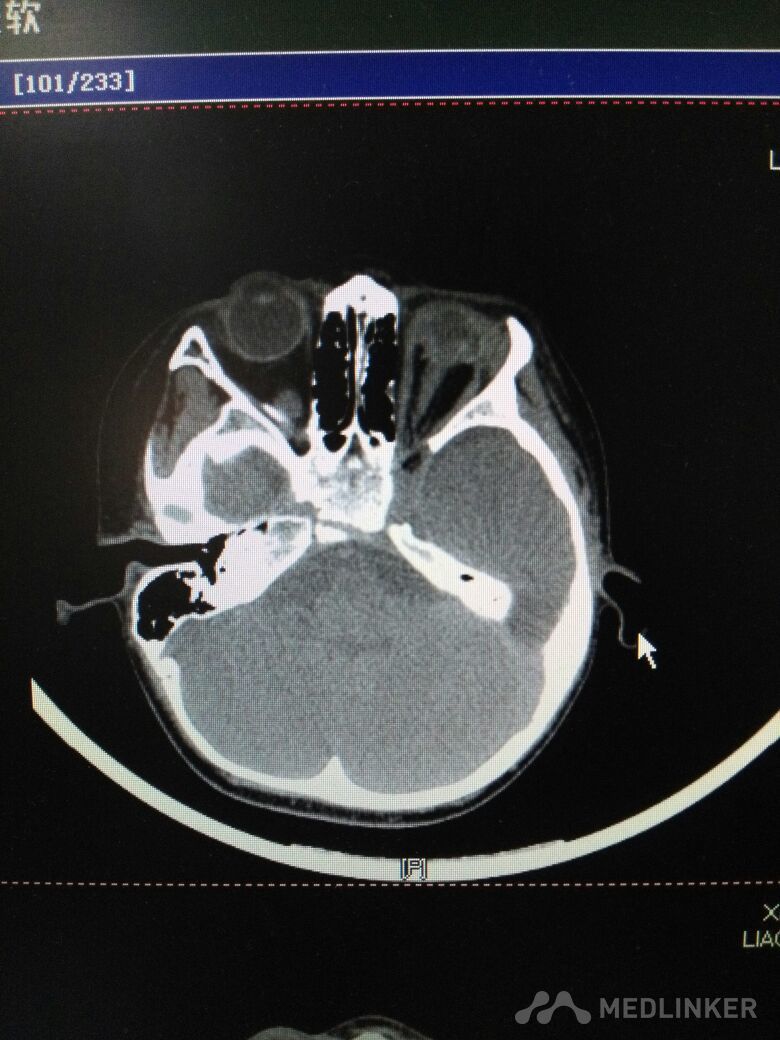

2岁男童,左眼外伤后11小时入院。不慎碰伤左眼,家属说不清是碗碎片还是碰到台阶上。父母在外省打工,奶奶带患儿从农村赶来。 检查不合作,做了急诊CT,左眼球正常形态消失,晶状体未见显示,眼内高密度影(考虑出血)。